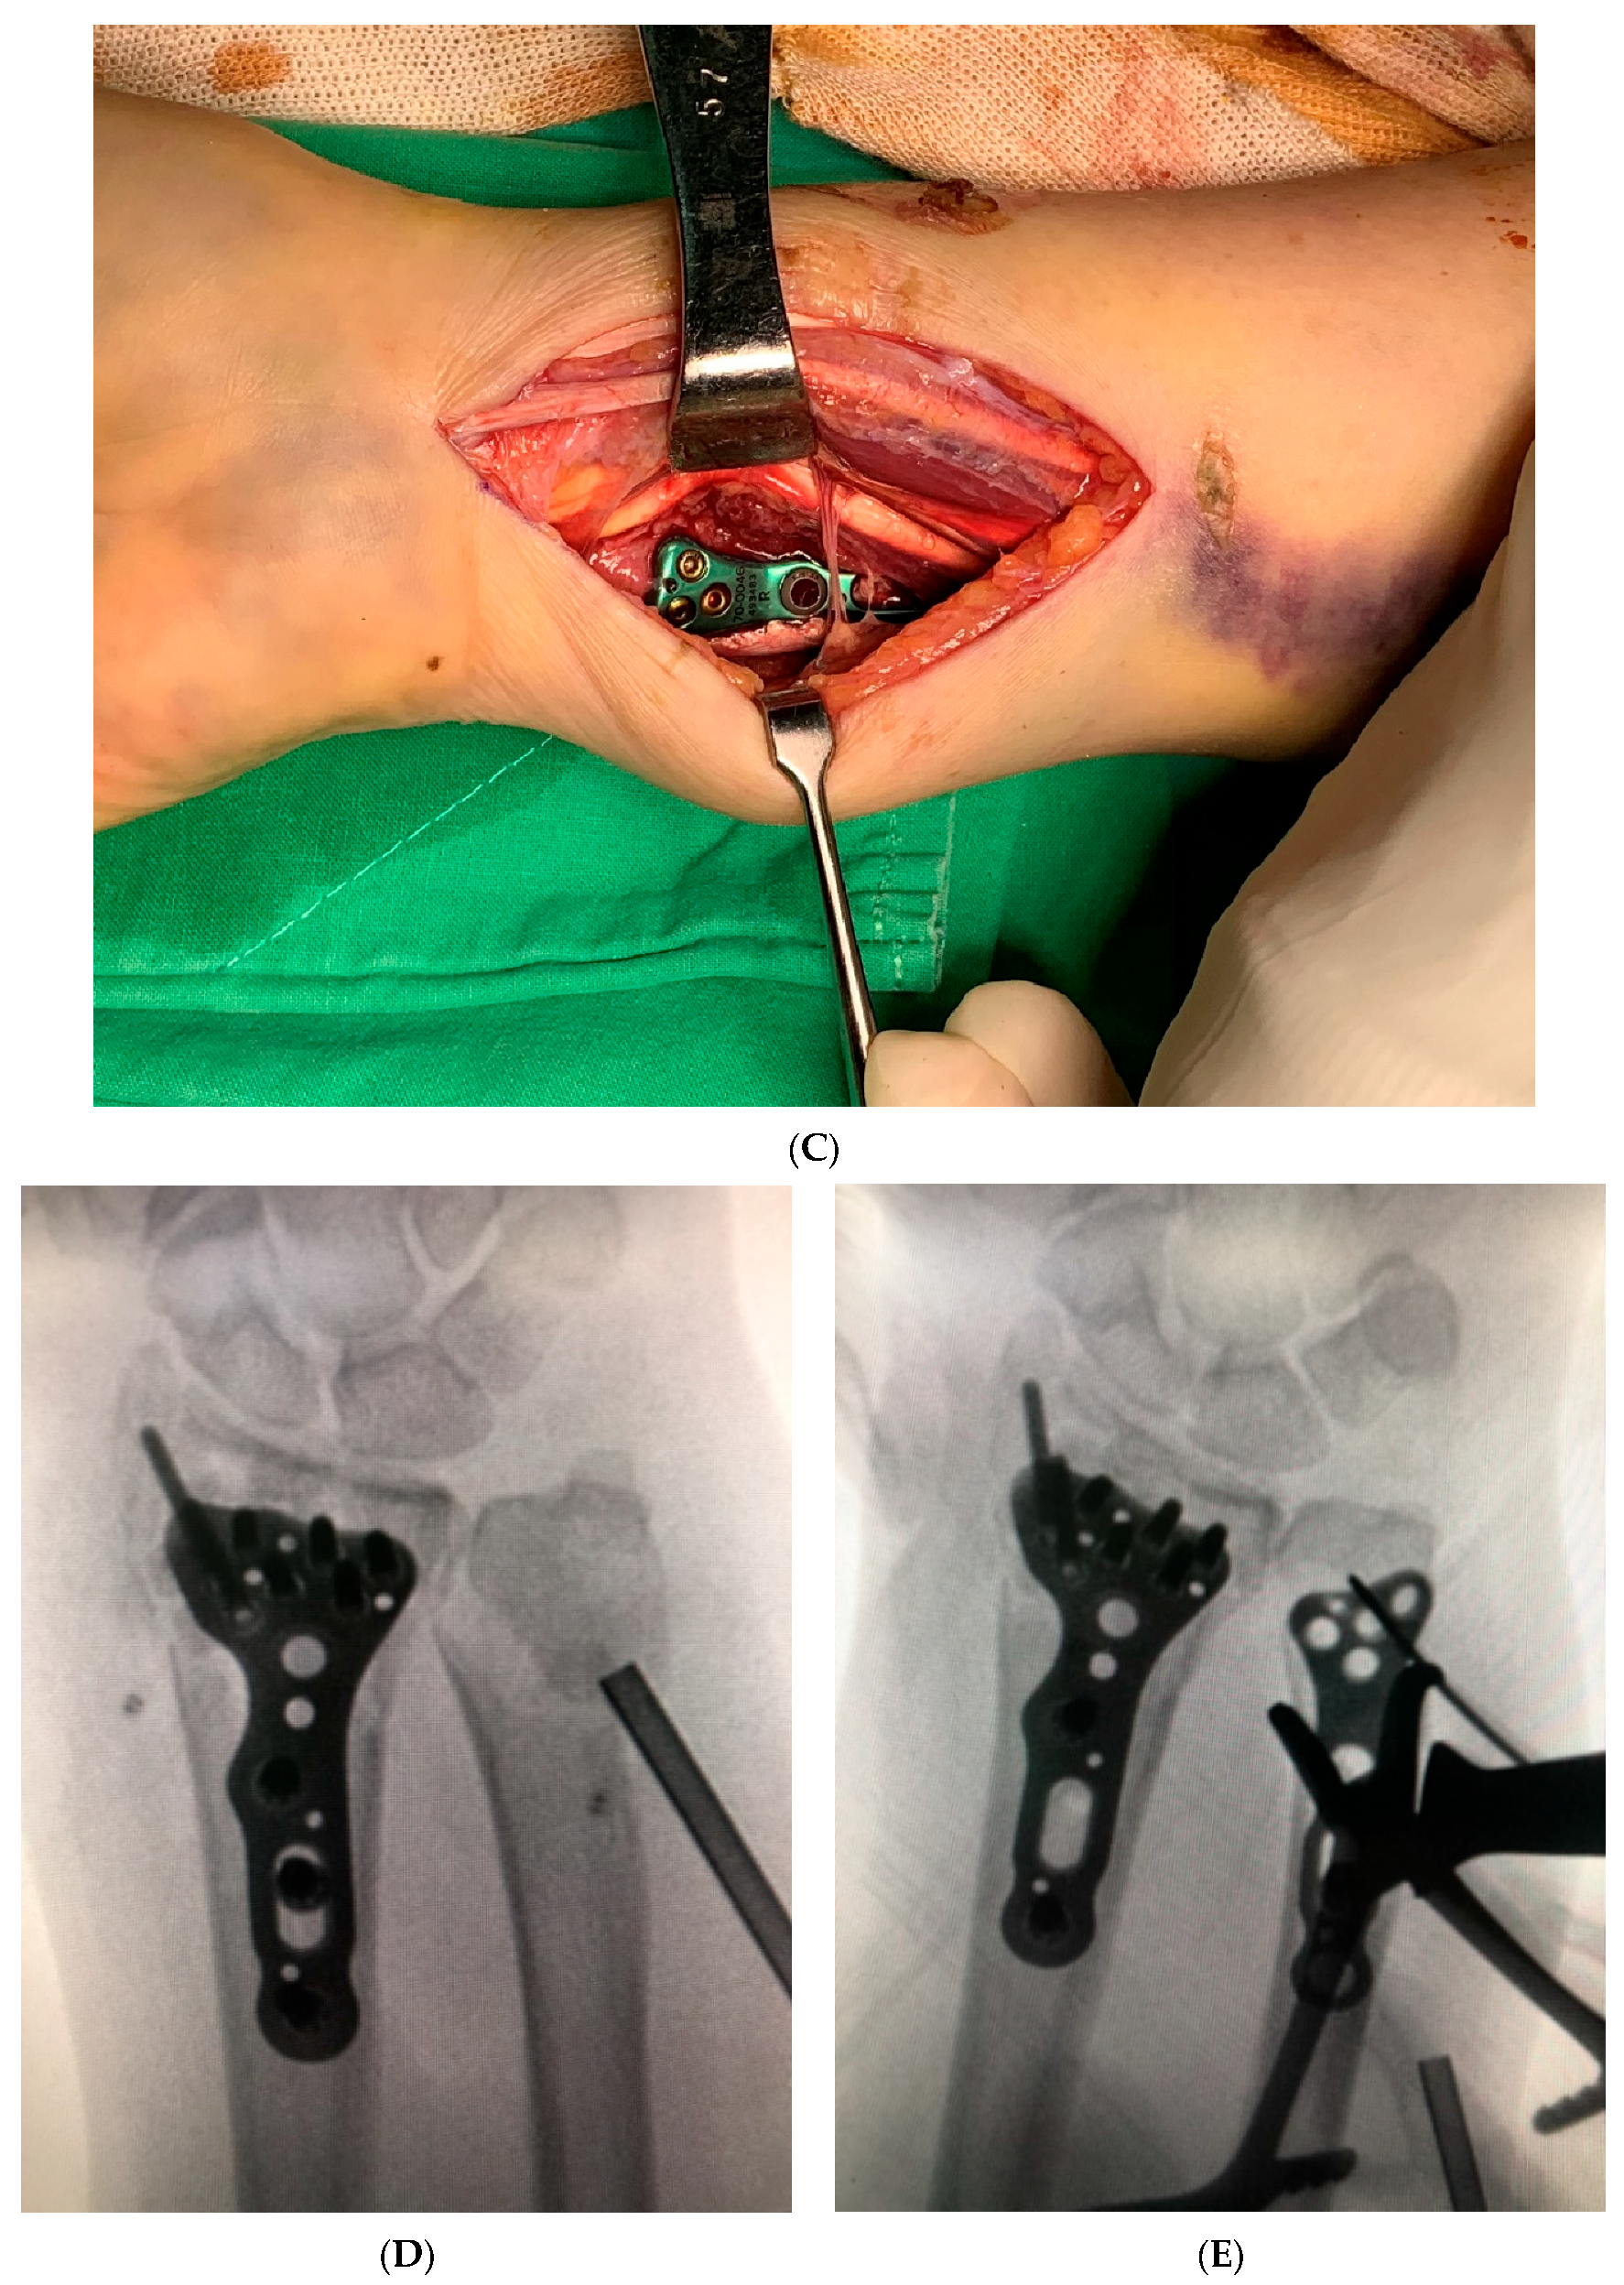

Figure 1.

The figures showed intraoperative images of initial fracture fixation through the modified dual window approach. (A) Straight skin incision is made between the interval of flexor carpi radialis (FCR) and palmaris longus (PL), which is around 8–9 cm; (B) ORIF of the radius was conducted through the lateral window. (C) ORIF of the ulna was conducted through the medial window. (D) fluoroscopy: anteroposterior view after final fixation of the DRF; check the alignment of the DUF. (E) fluoroscopy: DUF under ORIF with a point-to-point reduction clamp; the skin incision is made between the interval of FCR and PL.